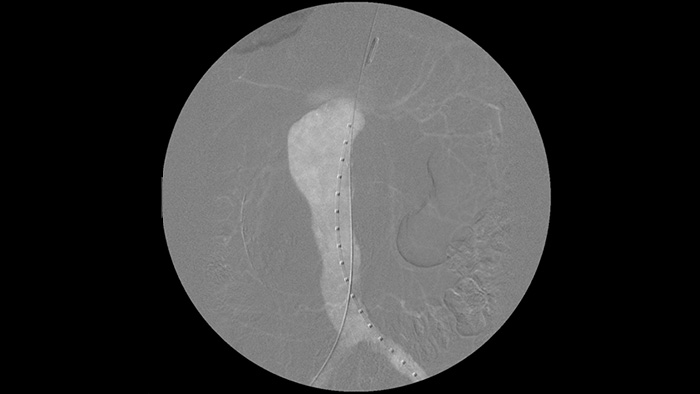

It’s easier to see a guide wire compared to our old system. Now you can see the tip and the angle of the wire that’s going around, even with 0.014 inch wires.

That’s because Zenition compensates for what’s metal and what’s moving."

Dr. R. Vila, MD

Bellvitge University Hospital, Barcelona, Spain

Digital subtraction angiography (DSA) is used in interventional vascular procedures to clearly visualise blood vessels by removing structures that can obscure vessel visibility. Roadmap fluoroscopy overlays a previously acquired subtracted contrast image on the live fluoroscopy, allowing you to track a device without reinjecting contrast.

As an addition to the Zenition 70 platform, the Touch screen module2 (TSM) supports table-side control for surgeons during procedures. Via the touchscreen, you can select, drag and zoom items with ease. This means you can view images instantly, giving you greater image control during procedures.